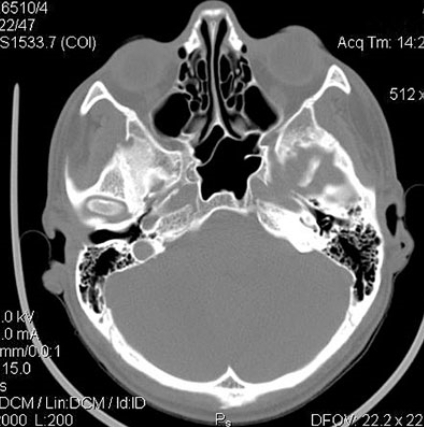

МРТ снимок придаточных пазух носа . МР-томография придаточных пазух носа . Лобная пазуха развита нормально, пневматизирована с четкими и плавными контурами стенок .

3 . Подготовка к МРТ придаточных пазух носа . 4 . КТ или МРТ носа, что лучше? Подготовка к МРТ придаточных пазух носа . Специфические мероприятия накануне не нужны . Слева — КТ-снимок одонтогенной кисты в верхнечелюстном синусе, справа — МР-фото образования . . .